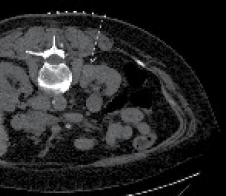

After adequate planning, 1% lidocaine is injected into the tract and an 18 gauge needle is left hubbed from the injection to determine whether it is in the vicinity of the mass. If properly positioned, this needle is exchanged for the RF probe after making a small incision. We prefer to use a 15-gauge RITA StarBurst probe (RITA Medical Systems, Mountain View, CA, USA) as the tine configuration permits visual confirmation that the entire tumor is enveloped. Figure 2 shows an example of how the tines appear deployed outside of the body and by CT scan. Under CT fluoroscopy guidance the probe is always inserted during a breath hold at end-expiration. The probe is advanced to puncture the tumor and then the tines are deployed rapidly. If inserted too slowly, the tines may not fully deploy. They should extend slightly past the tumor margin to ablate 0.5 cm beyond the mass. Near-perpendicular insertion of the probe on the mass is critical as it allows the greatest energy to be deposited at this deep margin where the region of highest blood flow is expected.

Figure 2. A) Before probe placement a CT scan is performed with IV contrast showing a 2.4 cm partially exophytic posterior ride sided tumor. B) The RITA StarBurst probe is shown with tines deployed. C) The configuration of the probe permits visual confirmation of coverage of the mass. Notice the ideal straight trajectory of the probe to the mass.